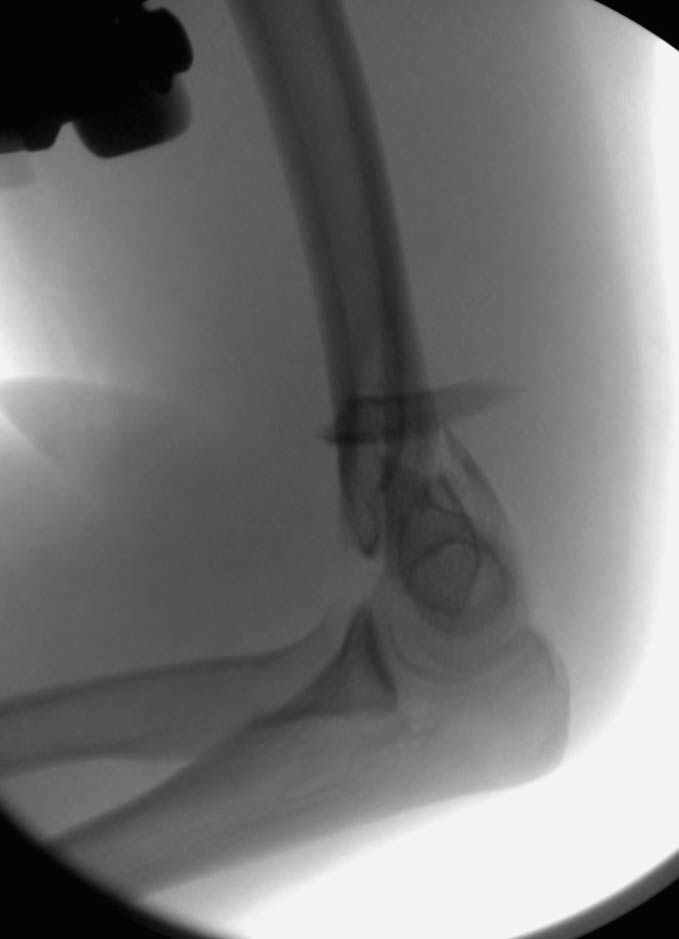

Примерный случай, только перелом был открытый, в задне-медиальной стороне рана около 2 см по характеру "изнутри кнаружи", неврологический статус со слабостью сгибания мизинца, также слабая абдукция и аддукция указательного пальца и сгибания в кисти.

Больному сделали обработку и наложили временный аппарат внешной фиксации плечо-предплечье.

На шестой день сделали открытую репозицию чрезлоктевым доступом двумя locking plate, локтевой нерв был ушибленным, после операции положительная динамика в Flexor Carpi Ulnaris. Фиксацию локтевого отростка произвели tension band technique с дополнительным шурупом.

Этапы операции на снимках....